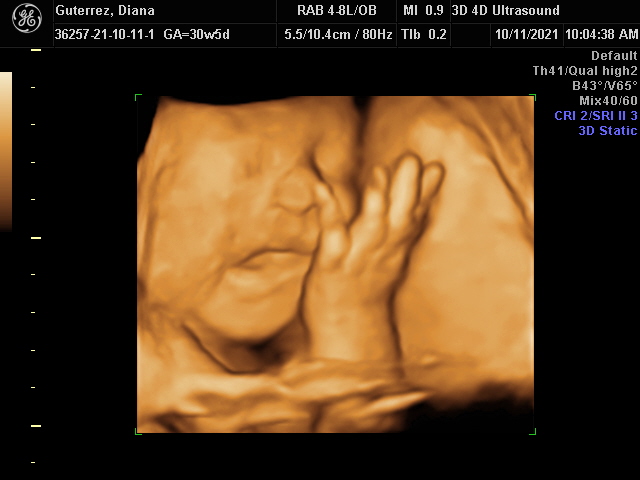

Our Gallery

Explore beautiful moments captured during our 3D and 4D sessions.